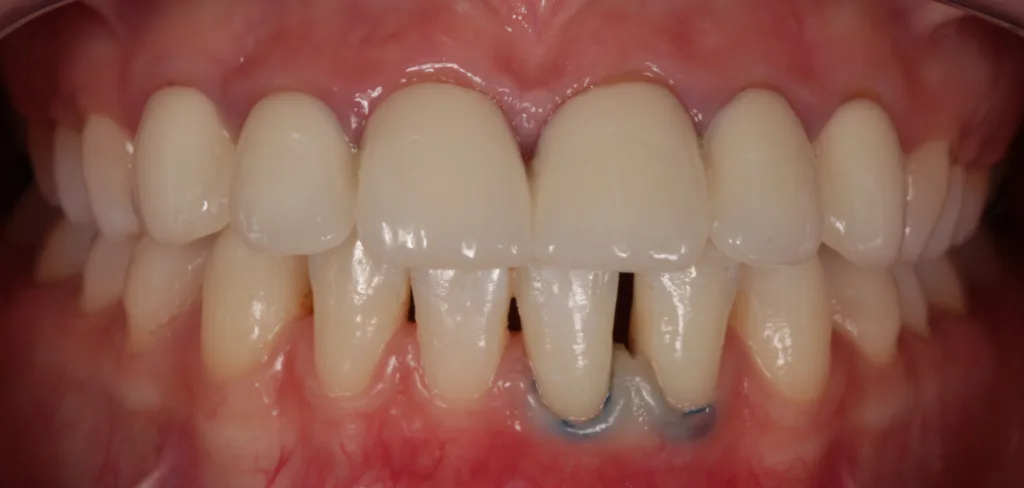

EggerIhr Wunsch bestand darin, die Lücke 31/32 mit möglichst einfachen Mitteln wieder ästhetischer zu gestalten (Abb. 2). Eine kieferorthopädische und/oder prothetische Variante kam aus finanziellen Überlegungen nicht in Betracht. Nach Aufklärung und eingehender Beratung war die Patientin mit der vorgeschlagenen Behandlung einverstanden.

Nach Befundaufnahme und professioneller Zahnreinigung wurde ein CMD-Kurzscreening durchgeführt und ein Fotostatus erstellt. Ein intraorales Mock-up [2] wurde auf Wunsch der Patientin und aus Kostengründen nicht angefertigt. Definitive Versorgung Adhäsivrestaurationen mit Komposit an 31/32 zum Schluss des Diastema laterale (Abb. 3 bis 9).

Grundsätzlich stand die Diskussion einer Gesamtsanierung (Austausch der insuffizienten Zirkonkronen aufgrund von Randspalten/Sekundärkaries, Entfernung retinierte 8er) im Raum. Die Patientin wünschte sich jedoch lediglich den Diastemaschluss im seitlichen UK-Frontzahnbereich und entschied sich nach Abwägung sowohl ethischer als auch finanzieller Aspekte vorerst nur für die Korrektur/Verbesserung der Zahnstellung im Unterkiefer mit direkten freihändig geschichteten Kompositaufbauten an 31 und 32. Konservierende (Füllungstherapie, In-Office-Bleaching), kieferorthopädische (Alignertherapie) und prothetische (Austausch der Zirkonkronen 13 bis 23) Maßnahmen hat sie aus finanziellen Überlegungen vorerst zurückgestellt [3,4].

Die Zahnproportionen 31/32 erscheinen nach Aufbau mit Komposit insbesondere im mesiodistalen Bereich etwas „ausgeprägter“ im Vergleich zur kontralateralen Seite und sollten daher als Kompromiss betrachtet werden. Die leicht eingekerbten/gezackten Inzisalkanten wünschte sich die Patientin etwas geradliniger.

Es zeigen sich postoperativ leichte Irritationen der Gingiva, die durch das Legen der Retraktionsfäden/Ligaturen entstanden sind und sich nach Abheilung und Reifung im Interdentalbereich noch adäquat ausformen werden, um somit einem ansprechenden dentogingivalen Erscheinungsbild zu entsprechen.

Die Zahnform der beiden unteren Schneidezähne 31 und 32 entspricht nach Diastemaschluss nun den Wünschen der Patientin (Abb. 10).